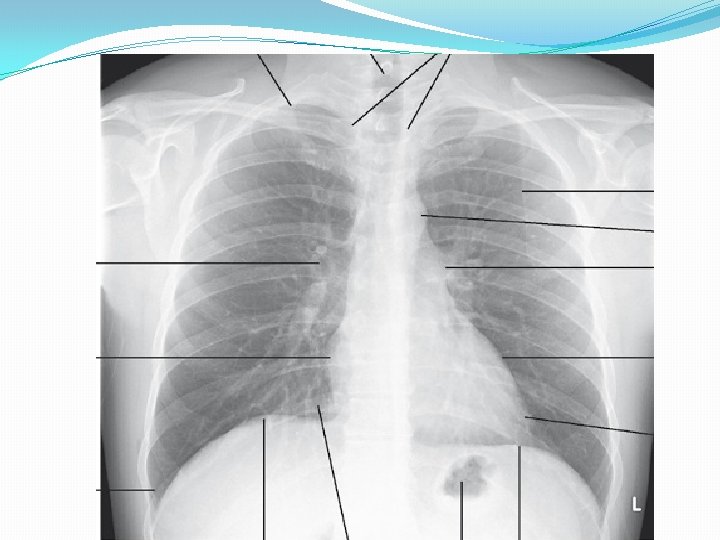

Chest X-RAY �Performed on the majority of patients �A postero-anterior (PA) film provides information on the lung fields, heart, mediastinum, vascular structures and the thoracic cage

�Lateral film, is requested if pathology is suspected behind the heart shadow or deep in the diaphragmatic sulci �Increased shadowing may represent accumulation of fluid, lobar collapse or consolidation

�Consolidation does not change the position of the mediastinum �Presence of an air bronchogram means that proximal bronchi are patent �Collapse (implying obstruction of the proximal bronchus) is accompanied by loss of volume and displacement of the mediastinum towards the affected side

�Ring shadows (diseased bronchi seen endon), tramline shadows (diseased bronchi side-on) or tubular shadows (bronchi filled with secretions) suggests bronchiectasis �Pleural fluid is suggested by a shadow which, in the erect patient, ascends towards the axilla